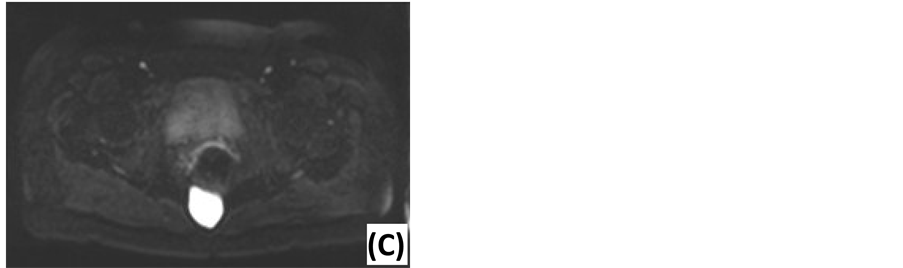

Preoperative work-up was done by MRI. Findings are summarized in Table 2 and propose a broad differential diagnosis. Examples are shown in Figure 2. Two diffusion-weighted MRI’s (DWI) were performed, using apparent diffusion coefficient (ADC) values at low (0 s/mm2) and high (1000 s/mm2) diffusion gradients. ADC values were high for both diffusion gradients (Figure 3). Five patients underwent computed tomography (CT) before MRI. Other technical investigations before MRI or CT included a positron emission tomography (PET), a transrectal ultrasonography (TRUS), a transabdominal ultrasonography and two anoscopies. No presacral lesions were found. TRUS illustrated dilated seminal vesicles. Transabdominal ultrasonography suggested acute appendicitis. One anoscopy revealed an anal fissure.

Figure 3. Diffusion-weighted MRI of an epidermoid cyst. (A) ADC map: low signal intensity. (B) DWI with low diffusion gradient (b = 0 s/mm2): high ADC value. (C) DWI with high diffusion gradient (b = 1000 s/mm2): high ADC value.

Due to the excellent soft-tissue resolution and multiplanar capacity, MRI is the best imaging modality to assess tumor location, size, morphology and adjacent structures [5] [6] [10] . The risk of malignancy can be estimated based on following features: heterogeneity, solid appearance, irregular or infiltrative borders, variable enhancement after gadolinium administration, rapid growth and extension above S3 [3] [5] [18] . Our findings predicted malignancy with 100% accuracy, confirming the current literature. Biological behavior also correlates with diffusion restriction. DWI can distinguish benign and malignant lesions, using quantitative ADC measurements. Several authors report significantly higher ADC values at high diffusion gradients for benign lesions [31] -[33] . Our findings concur with this conclusion. Specific diagnosis by MRI is difficult. Glasgow et al. report 28% of MRI diagnoses to be in accordance with the histological diagnosis [2] . Radiological evaluation provided a differential diagnosis in order of preference. Accuracy was 57.1%: two epidermoid cysts were mistaken for tailgut cysts and one tailgut cyst was mistaken for endometriosis. Presacral cysts usually have low signal intensity on T1-weighted images and high signal intensity on T2-weighted images. This may be influenced by the cyst’s content: blood, proteins and mucins cause higher signal intensity on T1-weighted images. Fat content is best seen on T1-weighted images using fat suppression. This is suggestive of a dermoid cyst. Tailgut cysts are multicystic, in contrast to other cystic masses. A chordoma is lobulated with a heterogeneous high signal intensity on T2-weighted images and low-intermediate signal intensity on T1-weighted images. Gadolinium injection reveals a heterogeneous enhancement with a honeycomb appearance [5] [18] [34] .